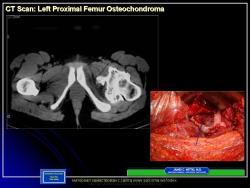

Наблюдение Соколиной И.А. и Зуевой М.А.

Приложения:

1.OHM_.Slayd9_.JPG2.OHM_.Slayd10.JPG3.OHM_.Slayd11.JPG4.OHM_.Slayd12.JPG5.OHM_.Slayd13.JPG